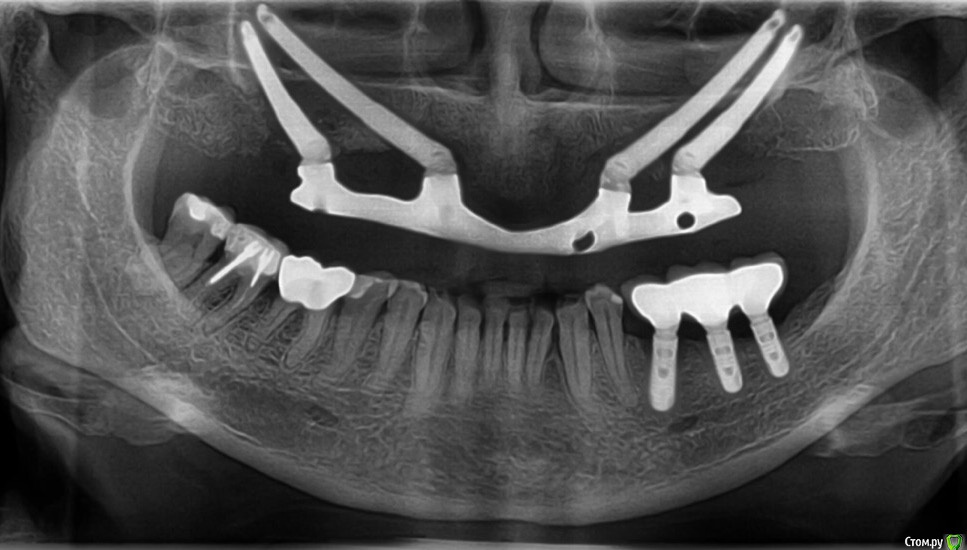

Maggie78rus Опубликовано 19 марта, 2017 Поделиться Опубликовано 19 марта, 2017 Обратилась в Клинику для исправления установленного мне моста, сказали, что по "ортопедическим показаниям" надо удалить стоящие у меня имплантаты и установить 4 зигомы. За год не смогли сделать протез, подходящий по прикусу, теперь к телефону не подходят, что делать- ума не приложу Обращалась за помощью к гнатолога, врач разбил выданные регистраты, чтобы не смогли проверить. Опять надо делать исследования... у кого-нибудь есть опыт установки протеза на зигомы на деформированную челюсть? Не знаю, как прикрепить фото и исследования гнатолога и кт суставов Ссылка на комментарий

Maggie78rus Опубликовано 20 марта, 2017 Автор Поделиться Опубликовано 20 марта, 2017 (изменено) https://drive.google.com/open?id=0B5M5deCMkPdRdExpV1RRdTRGZ3MВот, присоединила некоторые фотографии. Прошу извинить за демонстрируемый кошмар, поверьте, мне ещё и больно плюс я не могу держать равновесие Разыскиваю хорошего ортопеда в Санкт-Петербурге. Слышала много вариантов лечения вплоть до ортогнатологической операции и переделки конструкции заново на других имплантатах. Изменено 20 марта, 2017 пользователем Maggie78rus Ссылка на комментарий

Maggie78rus Опубликовано 20 марта, 2017 Автор Поделиться Опубликовано 20 марта, 2017 ортопед это и есть "протезист" Ортодонт вам не нужен. Зубов то нет. Честно говоря данных мало. Почему надо ставить зигомы не ясно.Мне тоже не совсем ясно, зачем мне удалили одни имплантаты и поставили на другие протез с такой же окклюзией. Все, конечно, путается в голове от этого нескончаемого кошмара и , извините, зубной боли, хотя зубов уже 2 года нет- потеряла после первого протезирования. Очень устала.Проблему с окклюзией, я получила 8 лет назад.Тогда я ничего не могла сделать, не могу сделать ничего и сейчас. Какое-то дежавю: милые стоматологи встречают меня с распростертыми объятиями, берут деньги, потом у них ничего не получается, т.к. все снимали анатомические слепки и по ним отливали мосты, а теперь протез... Никто не пользовался артикулятором и лицевой дугой. Я приходила к врачам, надеясь получить качественную стоматологическую помощь. Для установки скуловых имплантатов мне даже обещали использовать высокие шведские технологии трёхмерного моделирования... но, погрузив меня в медикаментозный сон, опять сняли оттиск и отлили протез по образу и подобию того, что я так стремилась исправить: страшного, маленького, заваленного то на один, то на другой бок.И так три раза. У меня отваливался то передний зуб, то клык...ничто не убеждало врача сделать дугу об'емнее...в конце-концов я настояла на диагностике у гнатолога, но диагностические модели разбили в окклюдаторе.В Клинике все врачи -специалисты широкого профиля да ещё и лекции читают, но мне-то они помочь не могут и не хотят: они уже получили все деньги, извините, обманом, а у меня ещё не стоит временный протез с нормальной окклюзией.Что делать? Ума не приложу! То, что зубов нет и ты не чувствуешь, как идёт нагрузка от зубов, думаю, неправда. Чувствуешь. Чувствуешь, как нёбный шов уходит в сторону...Попросила собрать консилиум врачей, чтобы помочь советами - результат один- делают оттиск, потом делают вид, что моделируют на воске, иногда получается здорово! Но потом ставят все тот же оттиск, но под другим углом Ссылка на комментарий

Maggie78rus Опубликовано 20 марта, 2017 Автор Поделиться Опубликовано 20 марта, 2017 У меня центр верхней и нижней челюстей не совпадают. Не знаю было так или нет. Потом у меня небо не плоское и деформированное от неправильной нагрузки на мосты , а теперь его протез на зигомах дожимает, больно Ссылка на комментарий

АнтонТЛТ Опубликовано 2 апреля, 2017 Поделиться Опубликовано 2 апреля, 2017 Выкладывайте оптг Ссылка на комментарий

Maggie78rus Опубликовано 2 апреля, 2017 Автор Поделиться Опубликовано 2 апреля, 2017 (изменено) Выкладывайте оптгСпасибо. Я первое фото с зеркалом не развернула Изменено 2 апреля, 2017 пользователем Maggie78rus Ссылка на комментарий